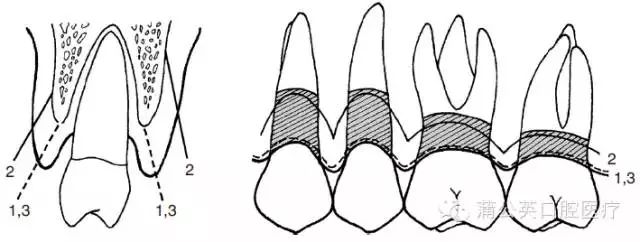

- 相邻的健康好牙会失去支撑,向缺牙空隙倾斜,移位,松动,相邻牙齿也

- 6,牙齿倾斜或牙齿长期缺损,导致相邻牙齿移位.

- 缺牙空隙内倾斜,移位,缺牙空隙相对应的牙齿将因无力量而逐渐伸长

- 缺失牙临近的牙齿向缺隙处倾斜

- 缺牙空隙内倾斜,移位,缺牙空隙相对应的牙齿将因无力量而逐渐伸长